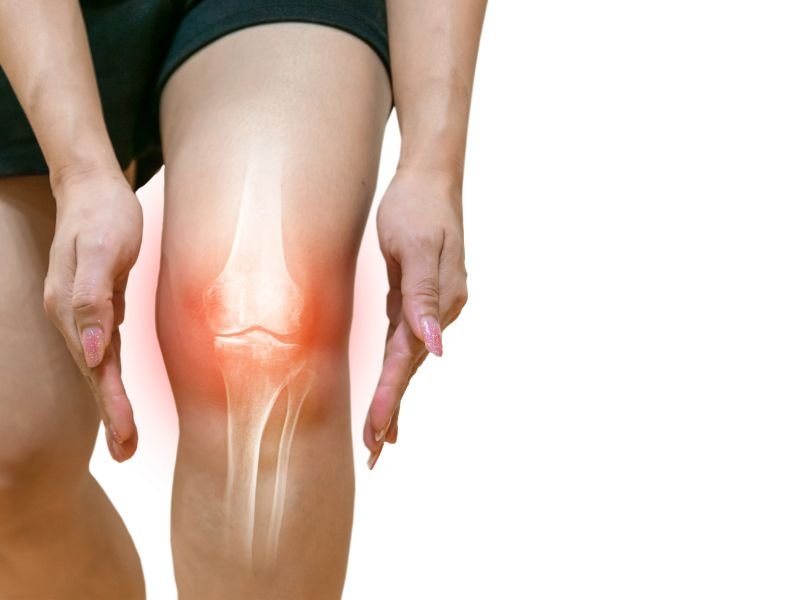

A adoção de um estilo de vida saudável é uma parte importante no tratamento e na prevenção das desordens articulares. Isso inclui manter um peso saudável, praticar exercícios físicos regularmente e adotar uma dieta equilibrada. A perda de peso pode ser particularmente benéfica para pessoas com osteoartrite, especialmente nas articulações dos joelhos, já que o excesso de peso coloca uma pressão adicional sobre as articulações.

- Manter um peso saudável: Reduzir a pressão sobre as articulações, especialmente as dos joelhos.